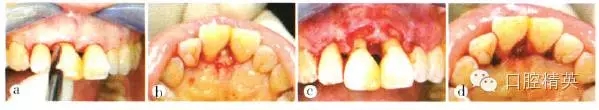

患者全身狀況良好,無過敏史及長期服用藥物史,否認吸煙史。口腔檢查:口腔衛(wèi)生尚好,菌斑、軟垢少,牙石+~++;個別牙齦輕度紅腫,出血指數(shù)(bleeding index,BI)為1~3,654 456牙齦退縮明顯;全口探診深度(probe depth,PD)3~5 mm,附著喪失,根分叉病變(furcation involvement,F(xiàn)I)個別1~2度,無松動;7缺失,1先天缺失,雙側(cè)第一磨牙近中關(guān)系。高位笑線,前牙I度深覆蓋,211牙冠呈尖圓形,牙齦退縮約1.3 mm,齦乳頭缺失,屬Miller III類.鄰面根頸部可見“黑三角”(圖1)。

a上前牙區(qū)正面觀;b上前牙區(qū)牙合面觀;c上前牙區(qū)腭側(cè)觀;d患者微笑像,可見上前牙區(qū)存在“黑三角”;e上前牙區(qū)側(cè)面觀

圖1初診時上前牙區(qū)口內(nèi)像及微笑像